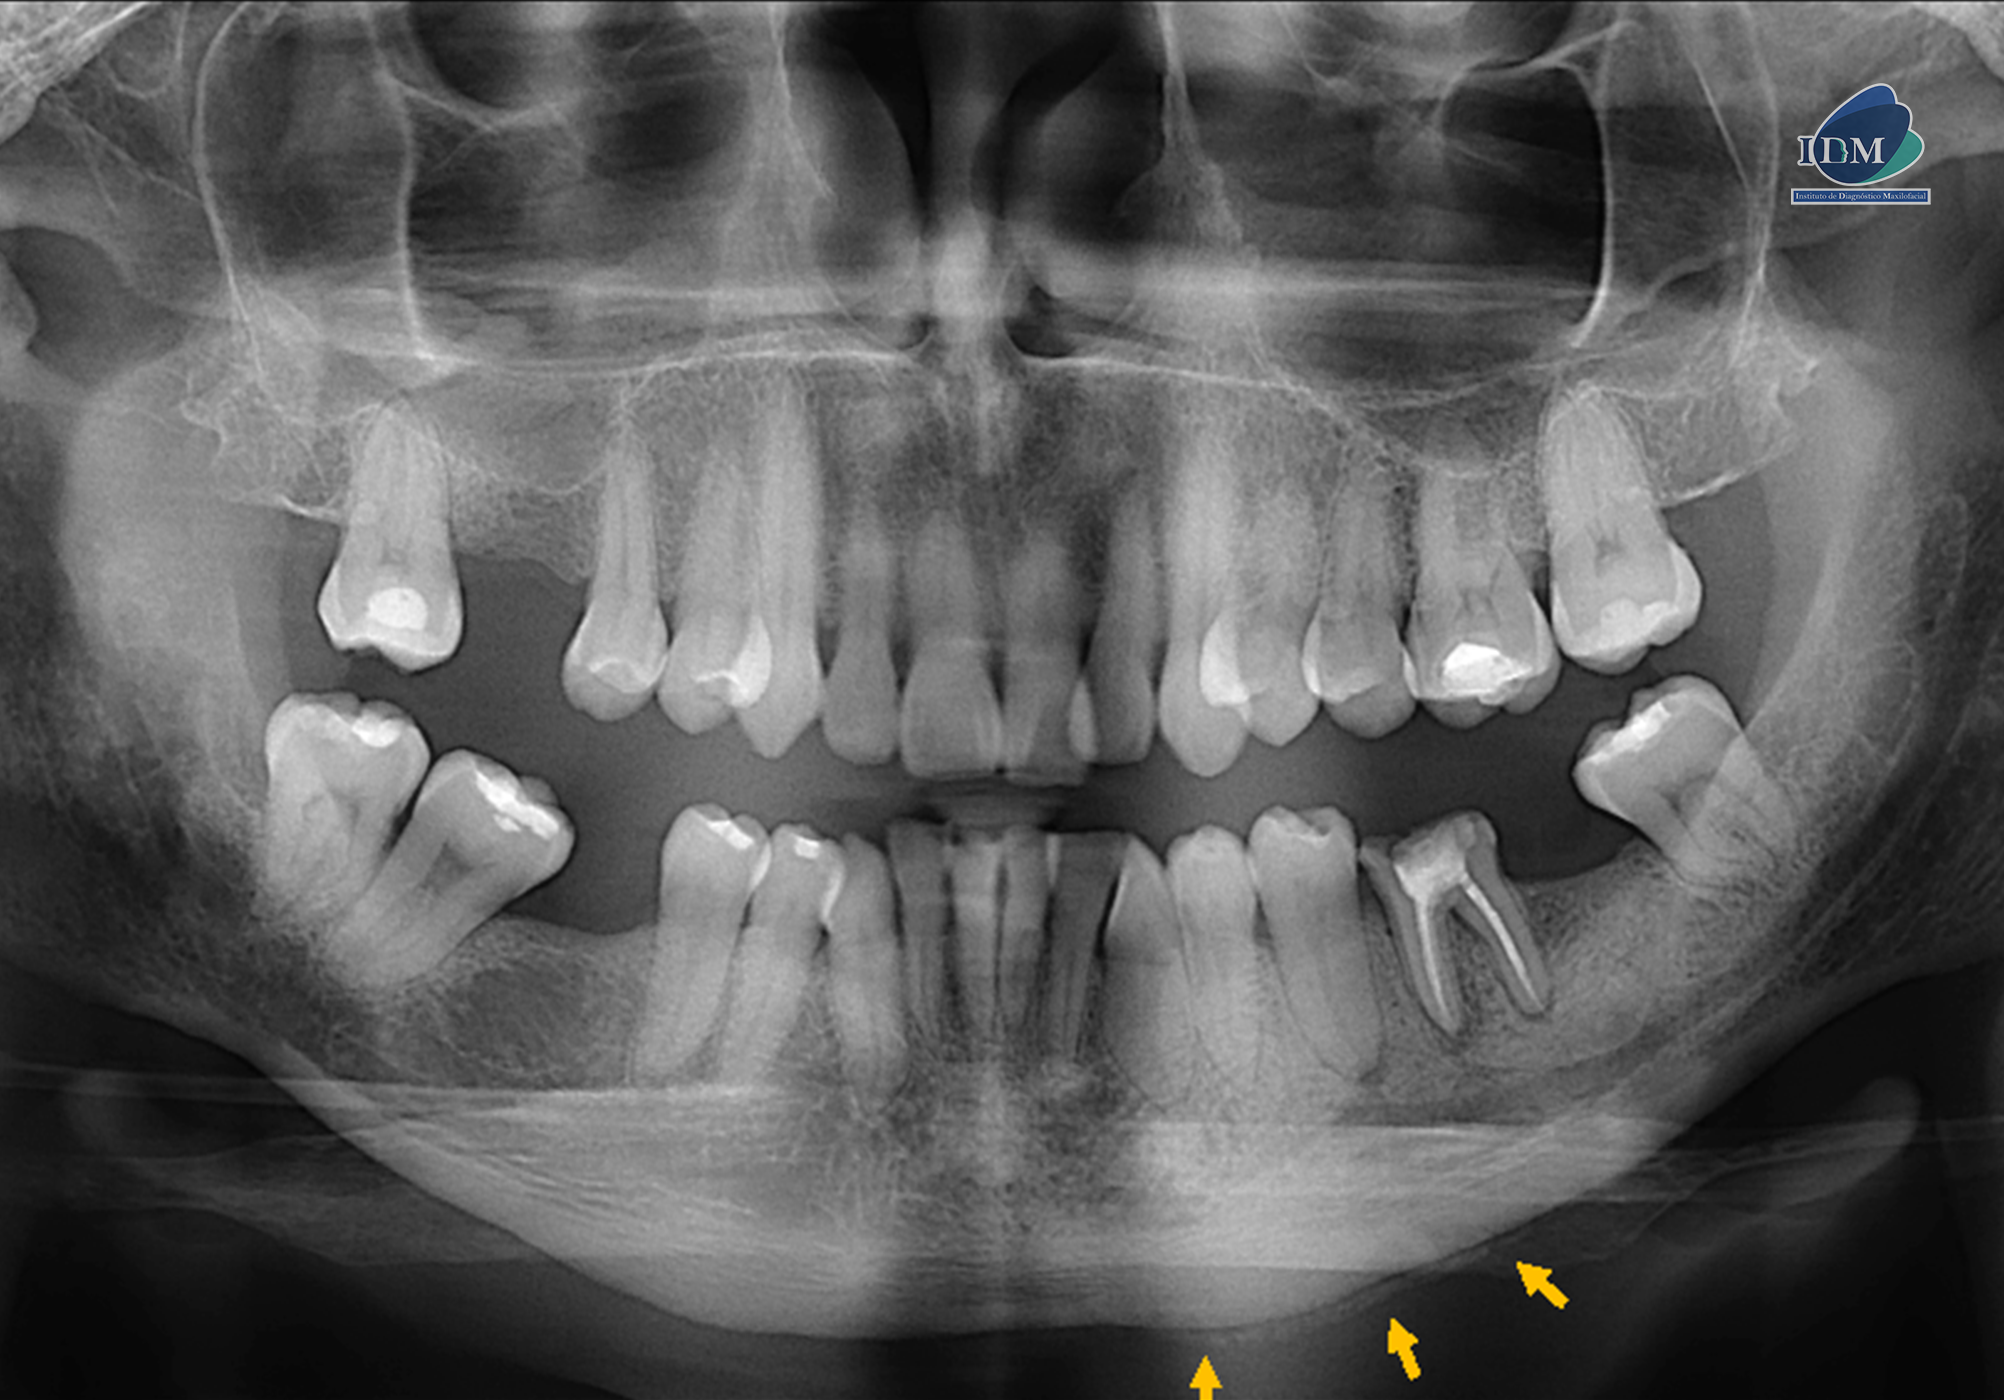

Radiografia Panorámica

En la radiografía panorámica se observa la pieza 36 con material restaurador coronario, obturación de conductos, proceso osteolítico periapical, acompañado de un aumento de la densidad ósea circundante que parece extenderse mesialmente hasta la pieza 34 y distalmente hasta la zona de la pieza 37, ocasionando el resalte del conducto dentario inferior y del agujero mentoniano izquierdo, el cual está proyectado sobre el ápice de la pieza 35. Además, se observa una reacción ósea perióstica en la basal mandibular adyacente a la zona afectada.